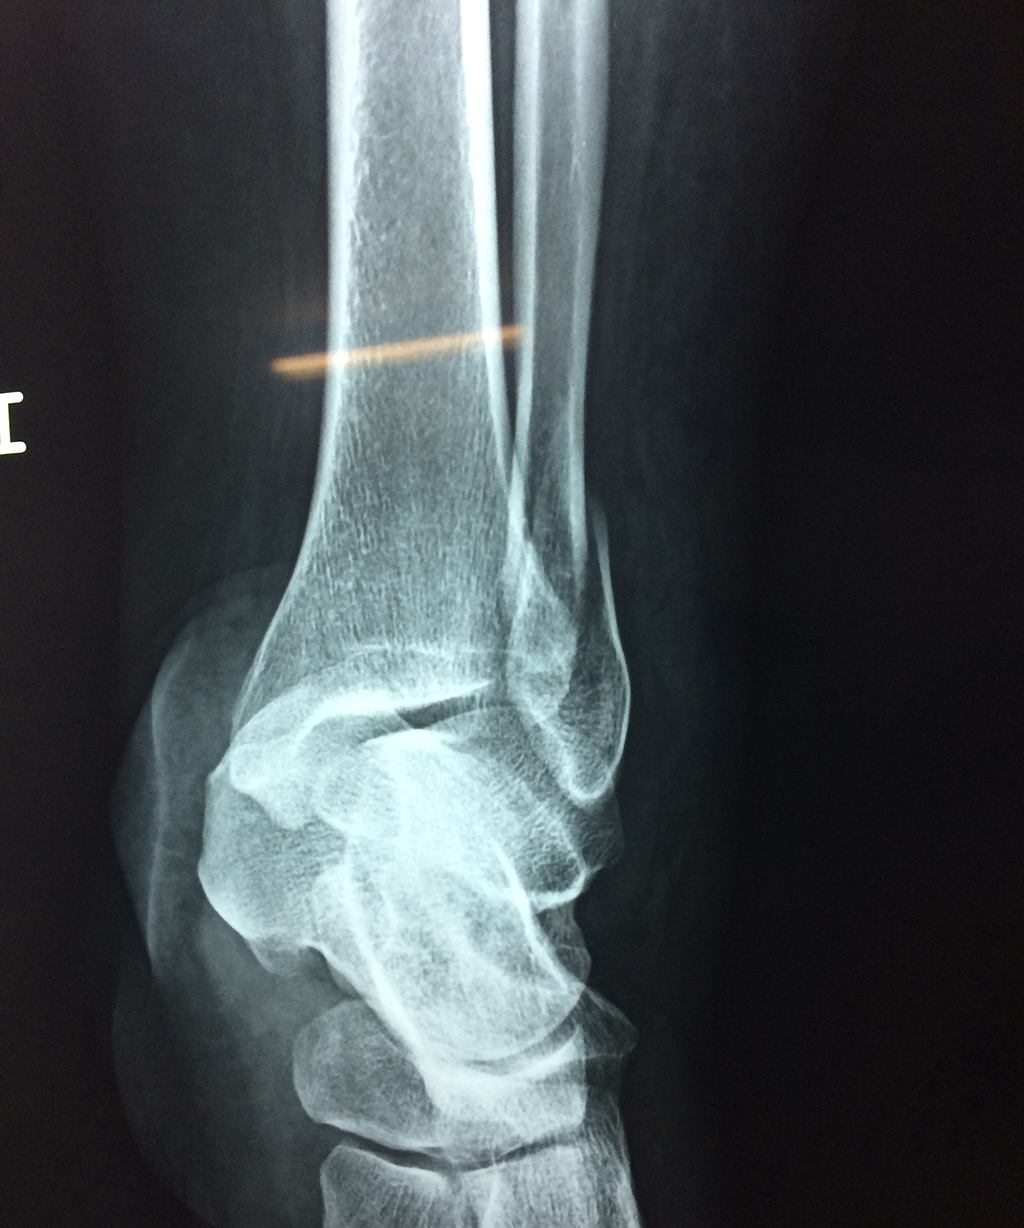

Una fractura de tobillo es la rotura de uno o más de los huesos del tobillo. Estas fracturas pueden ser:

Algunas fracturas de tobillo pueden requerir cirugía si:

- Los extremos de los huesos están desalineados entre sí (desplazados).

- La fractura se extiende hasta la articulación del tobillo (fractura intra-articular).

- Los tendones o ligamentos (tejidos que sujetan los músculos y los huesos entre sí) están rotos.